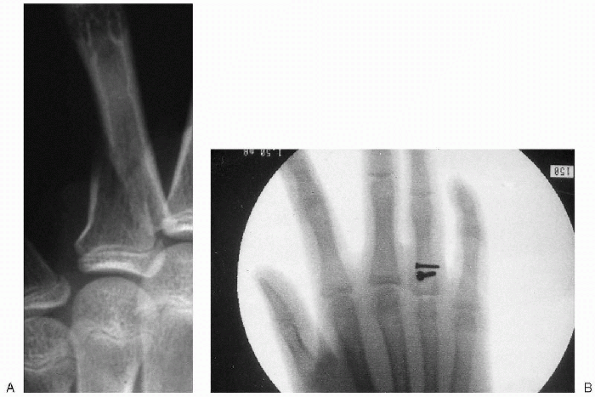

![]() |

Figure 12.4-2 Anterior radial head dislocation with apex anterior ulna fracture.

Figure 12.4-3 Torus, or buckle, fracture.

Figure 12.4-4 Greenstick fracture.

Figure 12.4-5 Complete fracture.